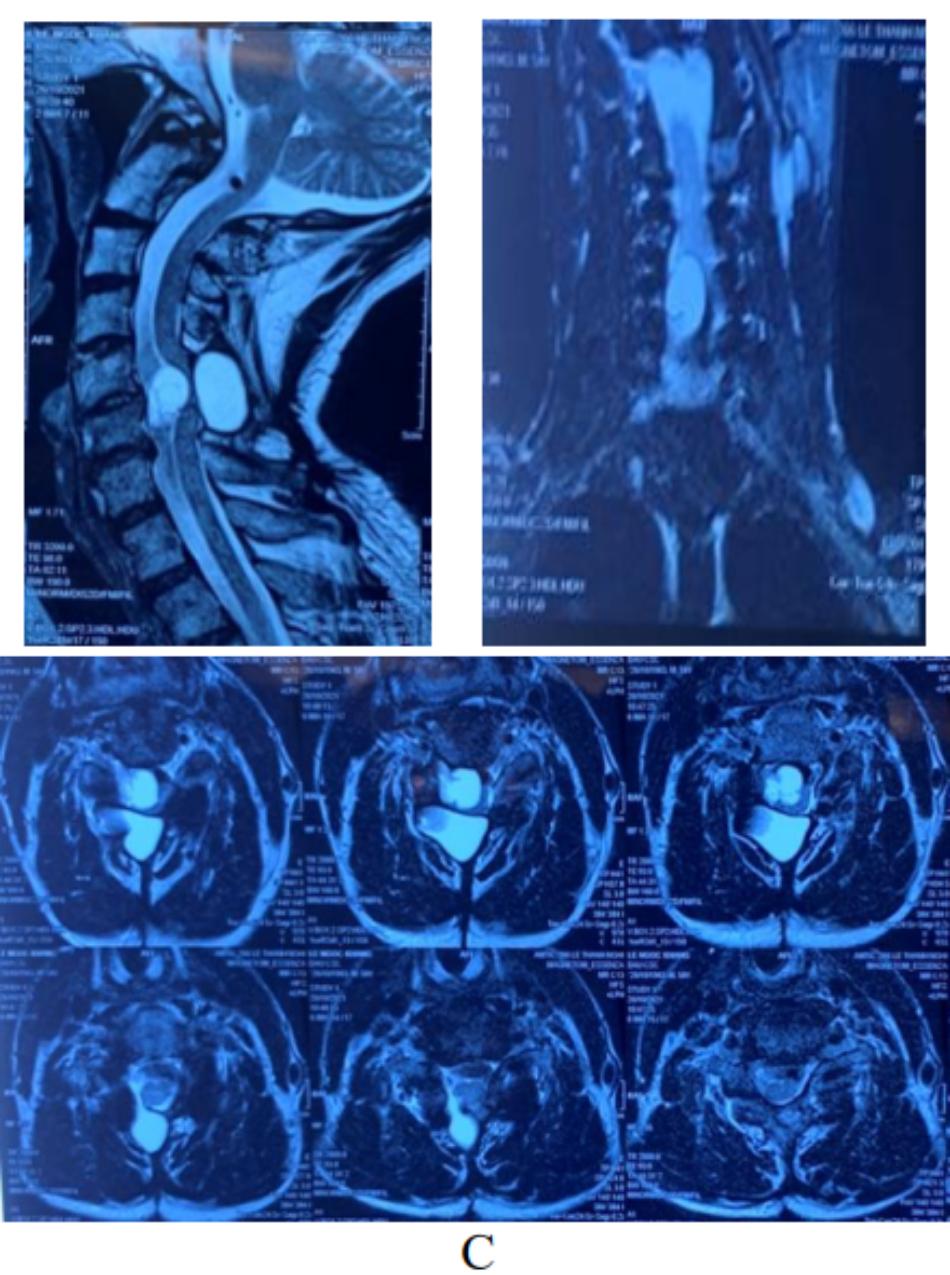

Ở lần phẫu thuật này, chúng tôi tiến hành phẫu thuật lấy u qua đường mổ cổ trước (Cắt thân C5-C6, lấy u, đặt lồng titan, ghép xương, cố định cột sống). Đại thể trong mổ, khối u dạng nang dưới màng cứng tương ứng đoạn tủy C5-C6, kích thước 25×12 mm, ranh giới rõ, không xâm lấn và phá hủy tổ chức xương (Hình 4A), dính một

(A) Khối u nang dưới màng cứng, dính một phần vào tổ chức tủy ngang C5-C6 (B, C) và hình chụp c.arm sau khi đặt lổng titan (D).

(A) mảnh cắt dạng nang, thành nang có một số đám tê bào hình thoi, nhân hình bầu dục, sắp xếp thành đám hướng đến Schwannoma tuyp nang hóa. Tiêu bản khối u ở mức phóng đại X 100 (B) và X 400 (C) gợi ý tuyp Antoni B

Sau mổ, bệnh nhân giảm dần cảm giác tê bì và phục hổi cơ lực tứ chi 5/5, sau 1 tuần có thể tự đi lại và sinh hoạt như bình thường. Ngày thứ 10, bệnh nhân được chụp MRI kiểm tra sau mổ. Trên MRI khối u nang chèn ép thần kinh nằm phía trước đã lấy bỏ, còn lại nang dịch ngoài màng cứng phía sau tủy, không gây chèn ép. Bệnh nhân được xuất viện ngày thứ 11 sau mổ và hẹn khám lại định kỳ 1,3,6, và 12 tháng sau mổ.